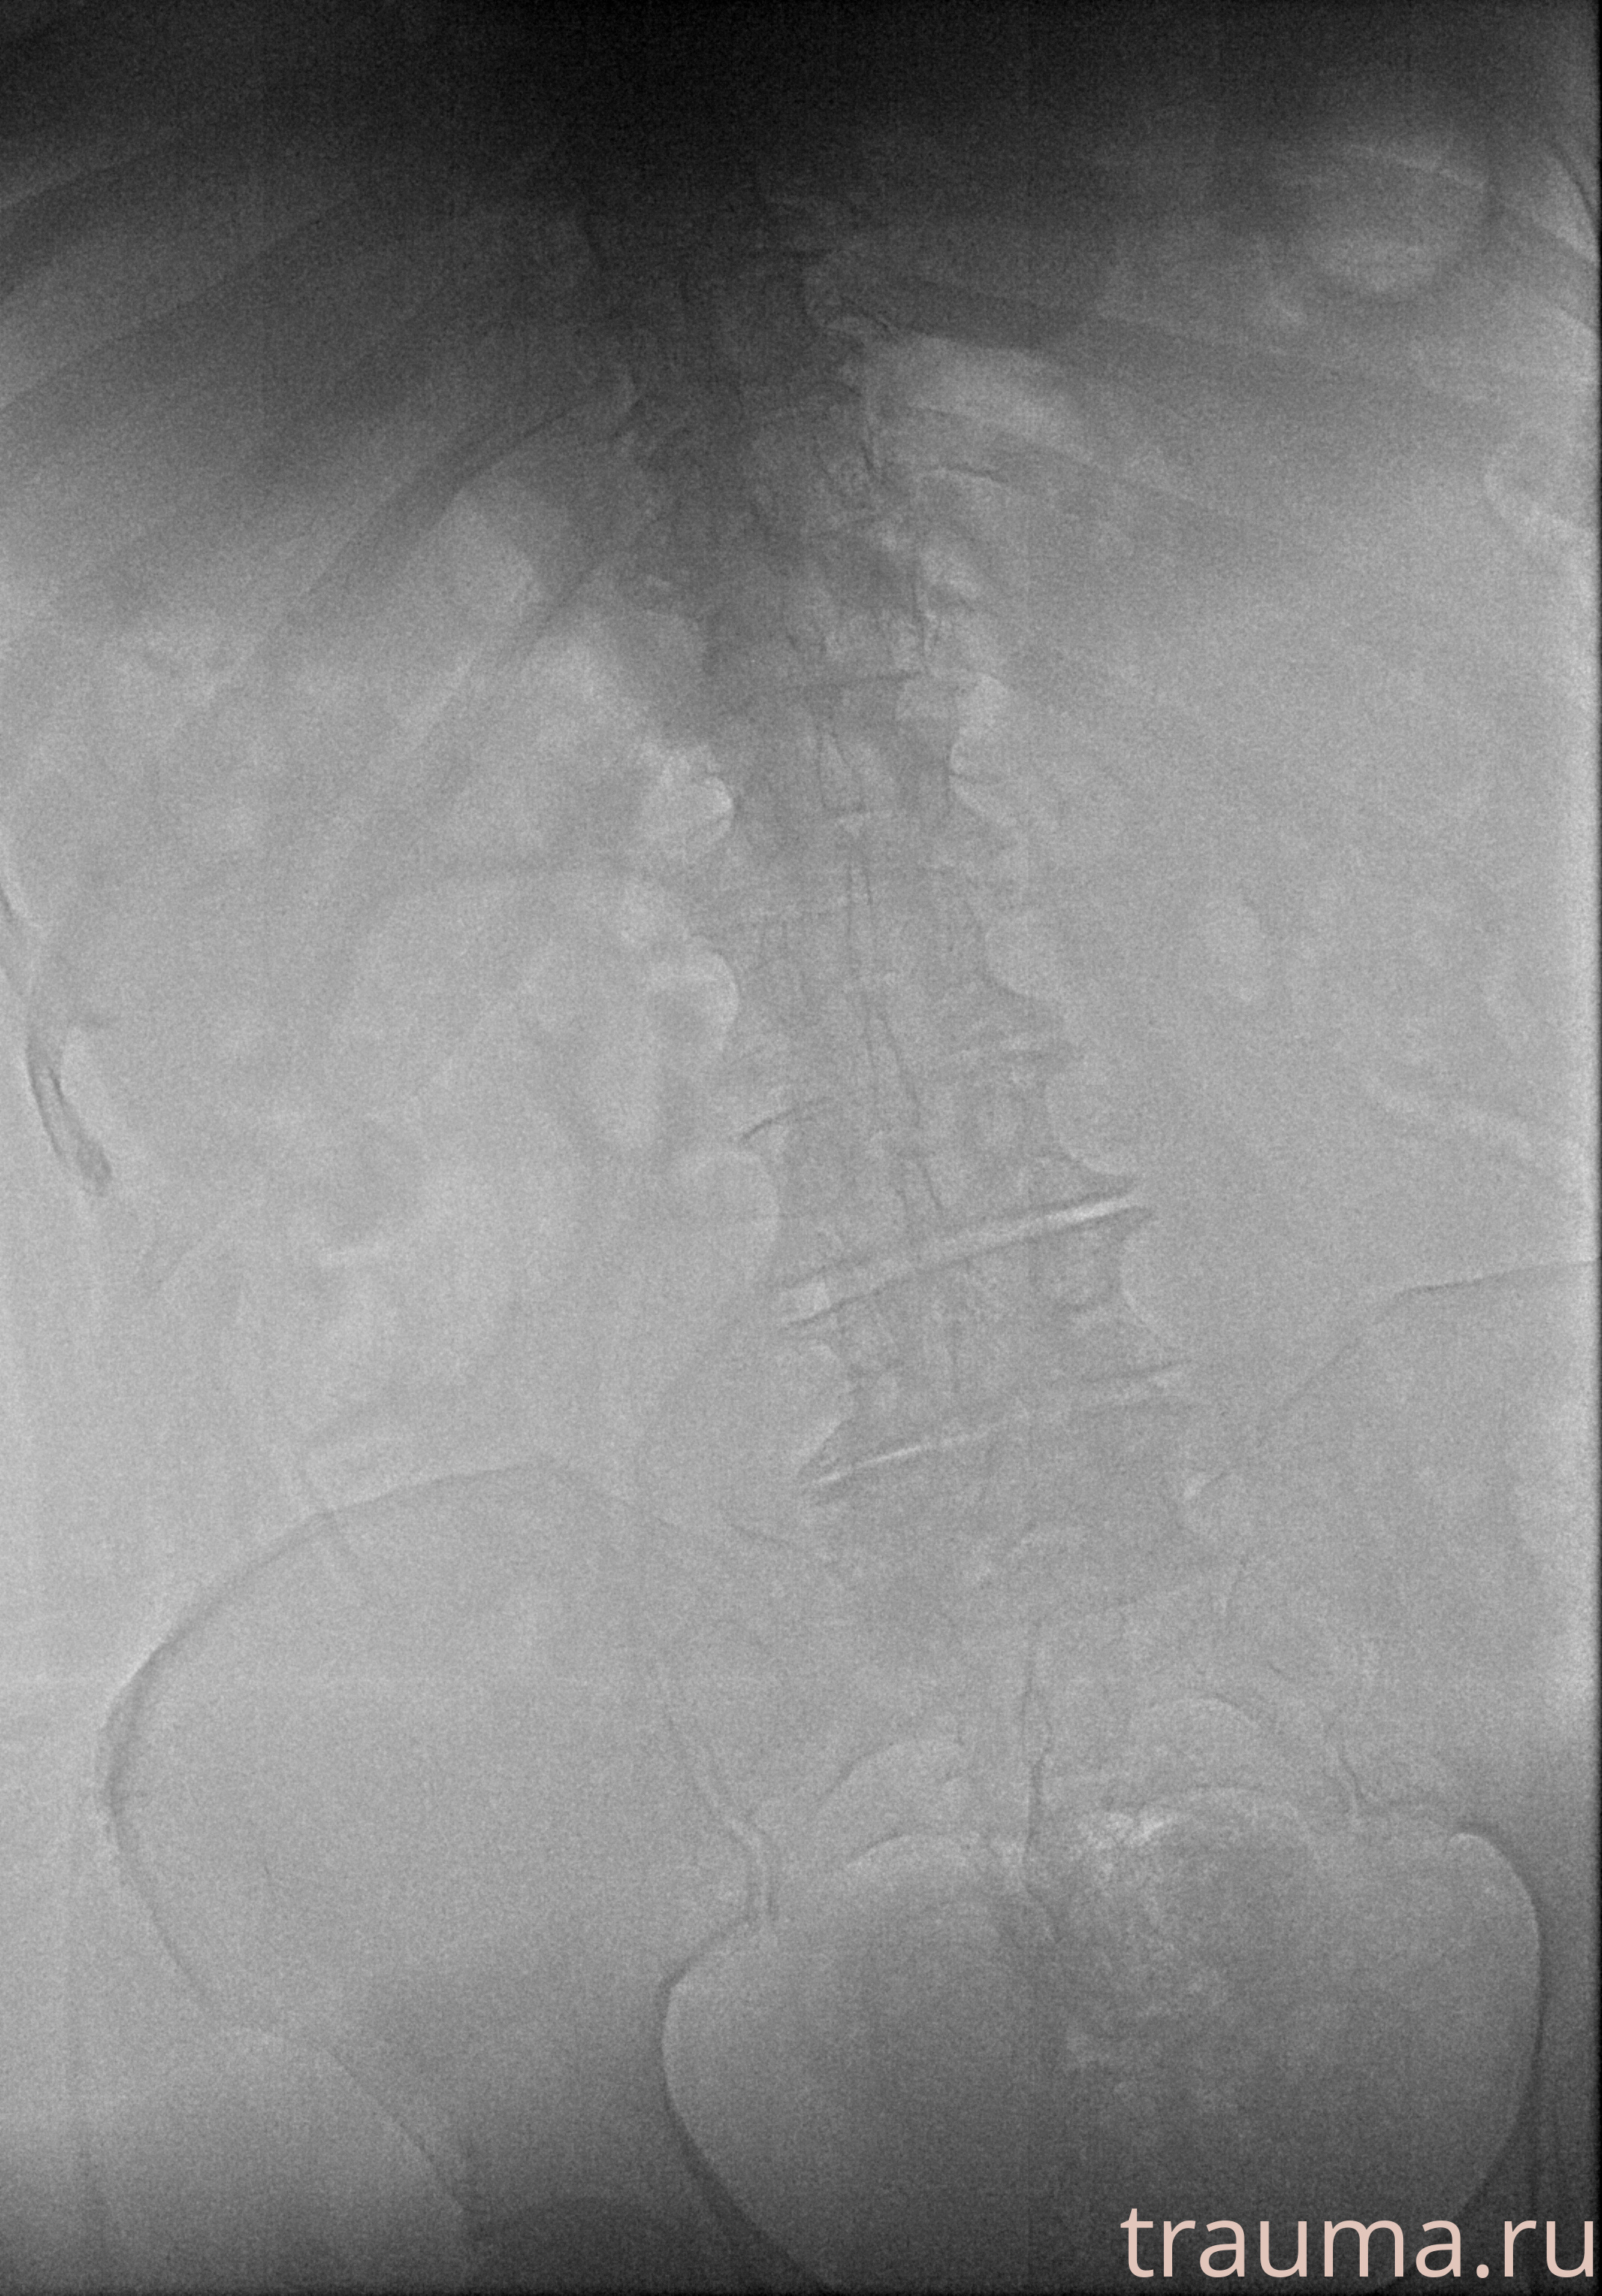

Рентгенограммы

Рентген на дому: по вашему адресу приезжает врач-рентгенолог, травматолог-ортопед с мобильным рентгеновским аппаратом, проводит диагностику травмы или заболевания, делает необходимые рентгенограммы, дает рекомендации по дальнейшему лечению. Получить качественные снимки в домашних условиях возможно благодаря уникальной методике, разработанной МосРентген Центром для института  Склифосовского